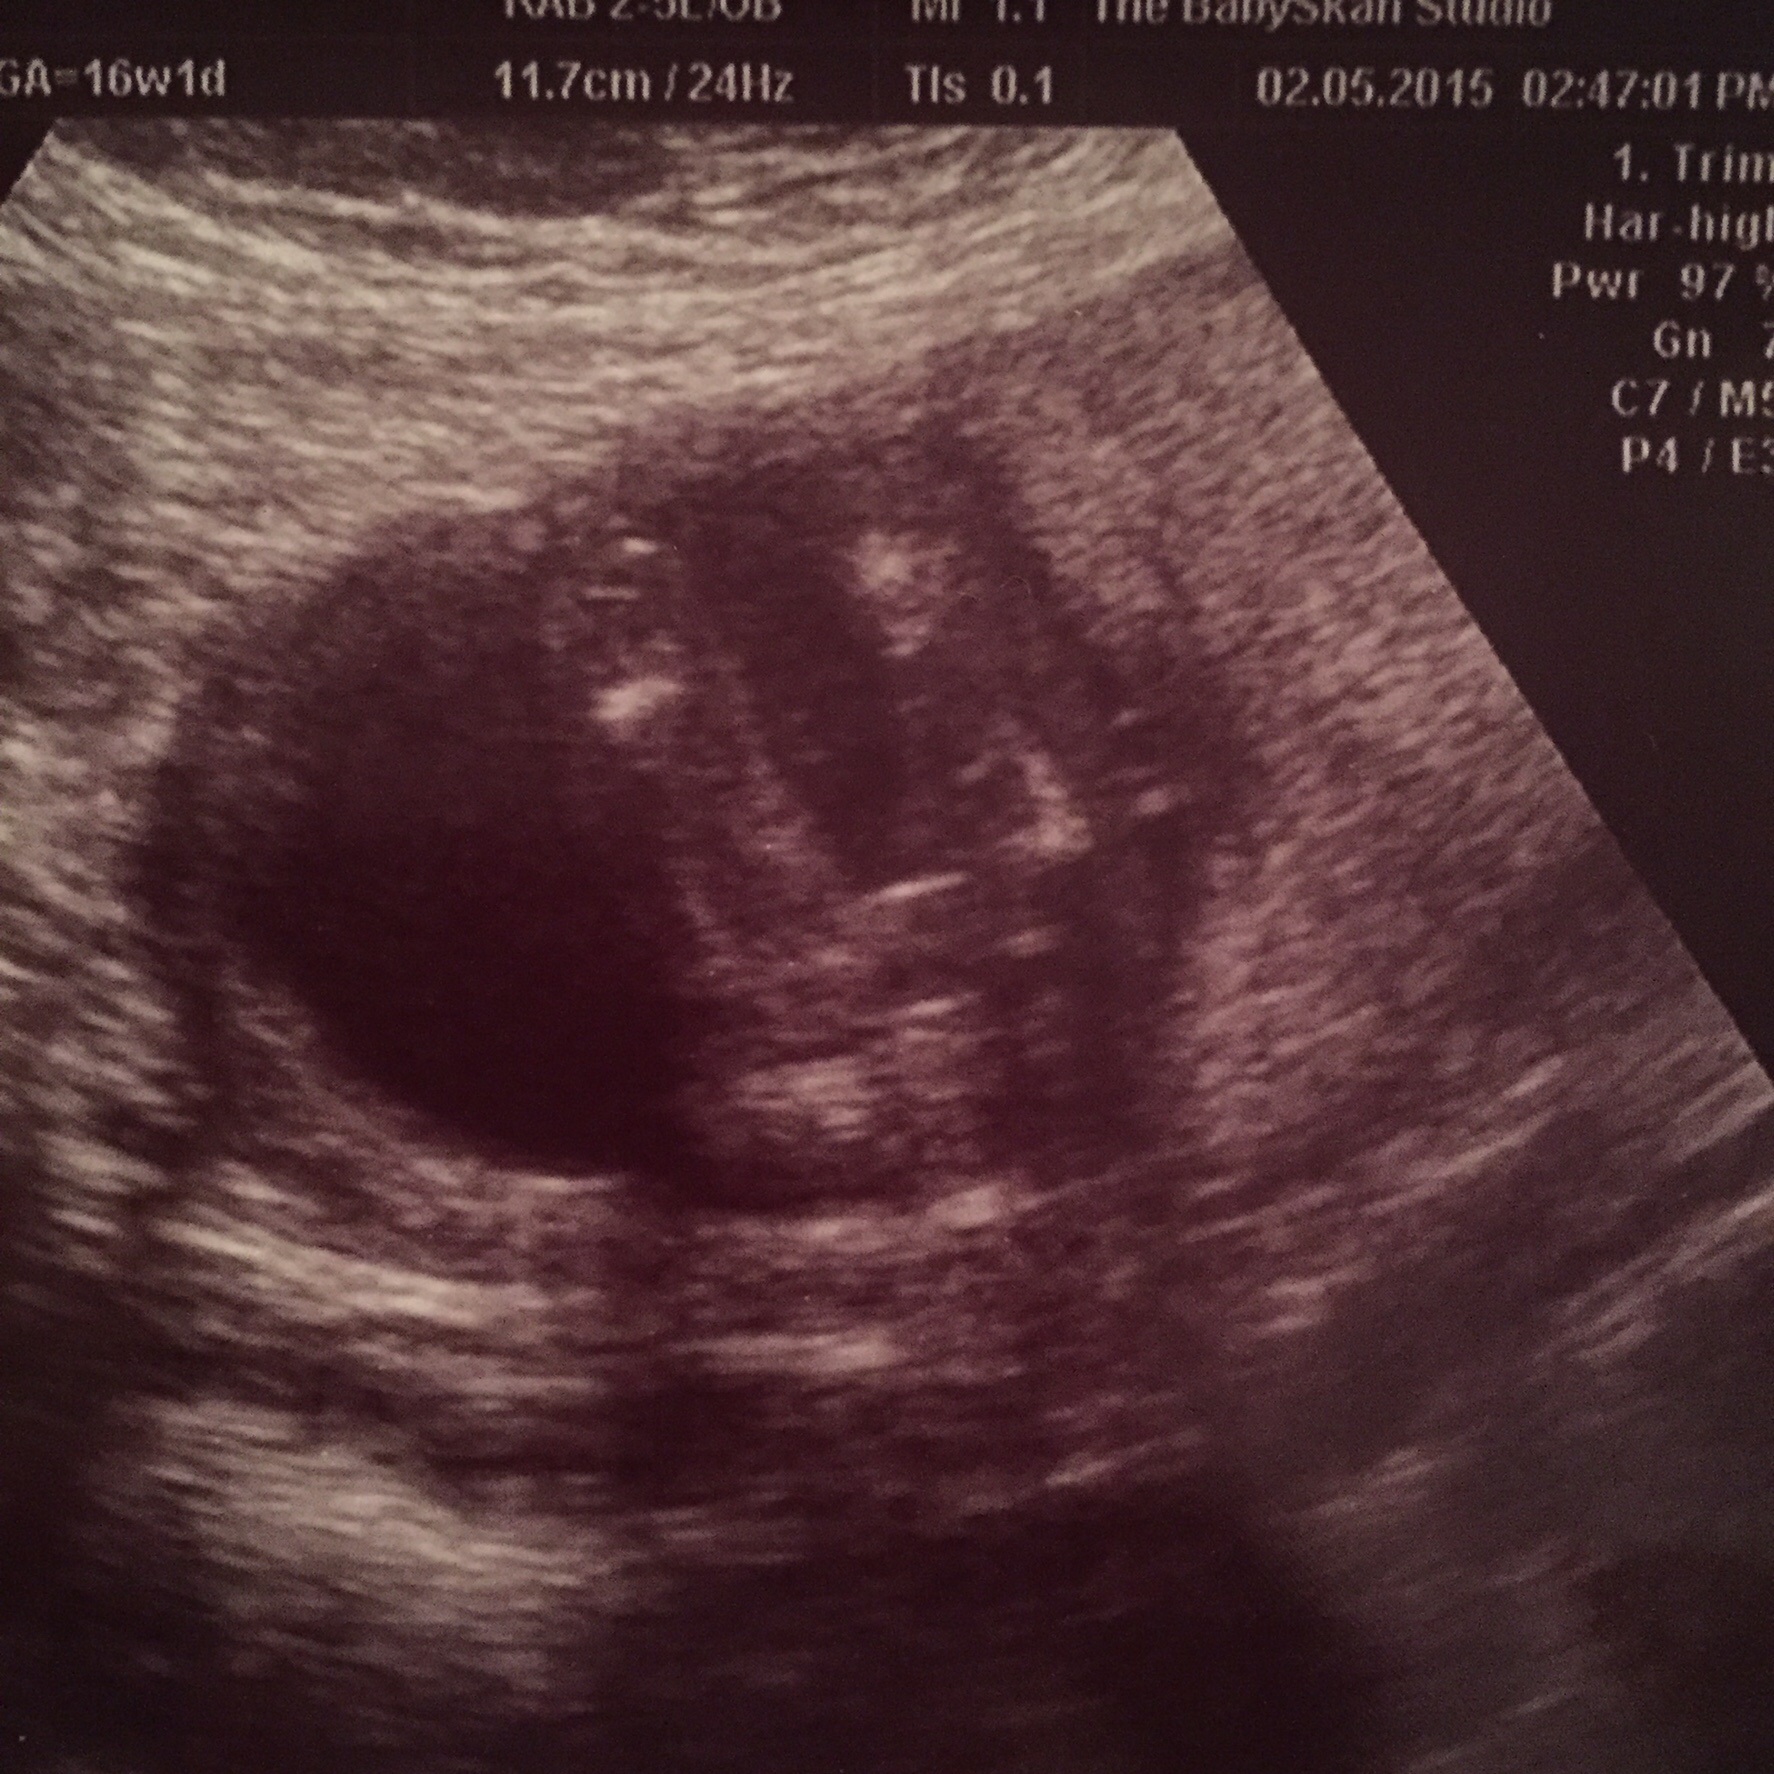

Going out of my mind... And want to be sure.. Potty shot taken at 16.1 weeks